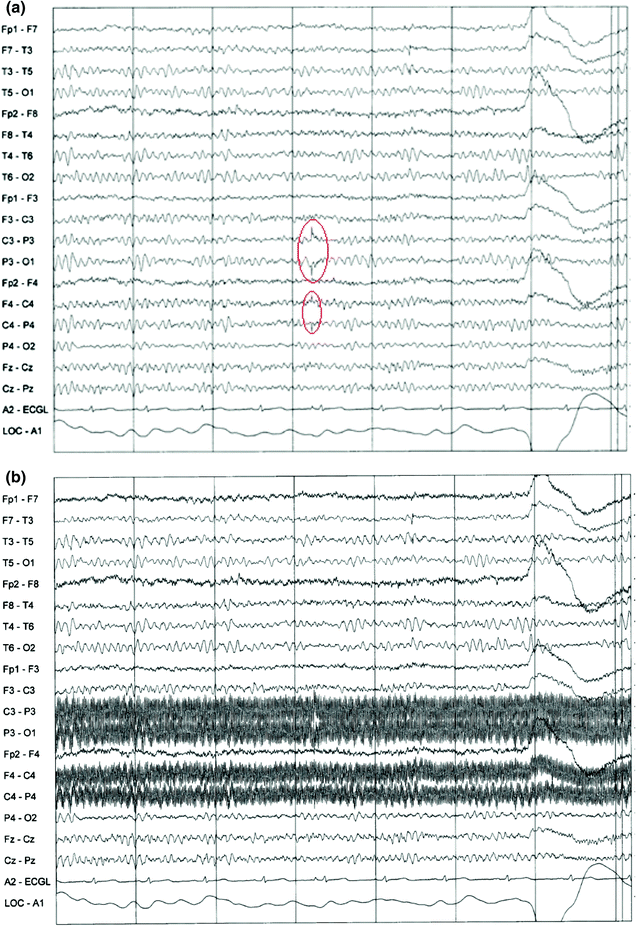

(a) EEG signals with heliumpump artifacts across several electrodes Eeg Electrode Pop Artifact — noise and artifacts are an unavoidable aspect of eeg recordings. — artifact removal is an especially common practice for a. temporary detachments of the recording electrodes (called “electrode pop” artifact) can further erode the eeg, or even imitate. — this chapter defines and gives examples of physiologic artifacts such as ekg, pulse, pacemaker, eye movements,. Eeg Electrode Pop Artifact.